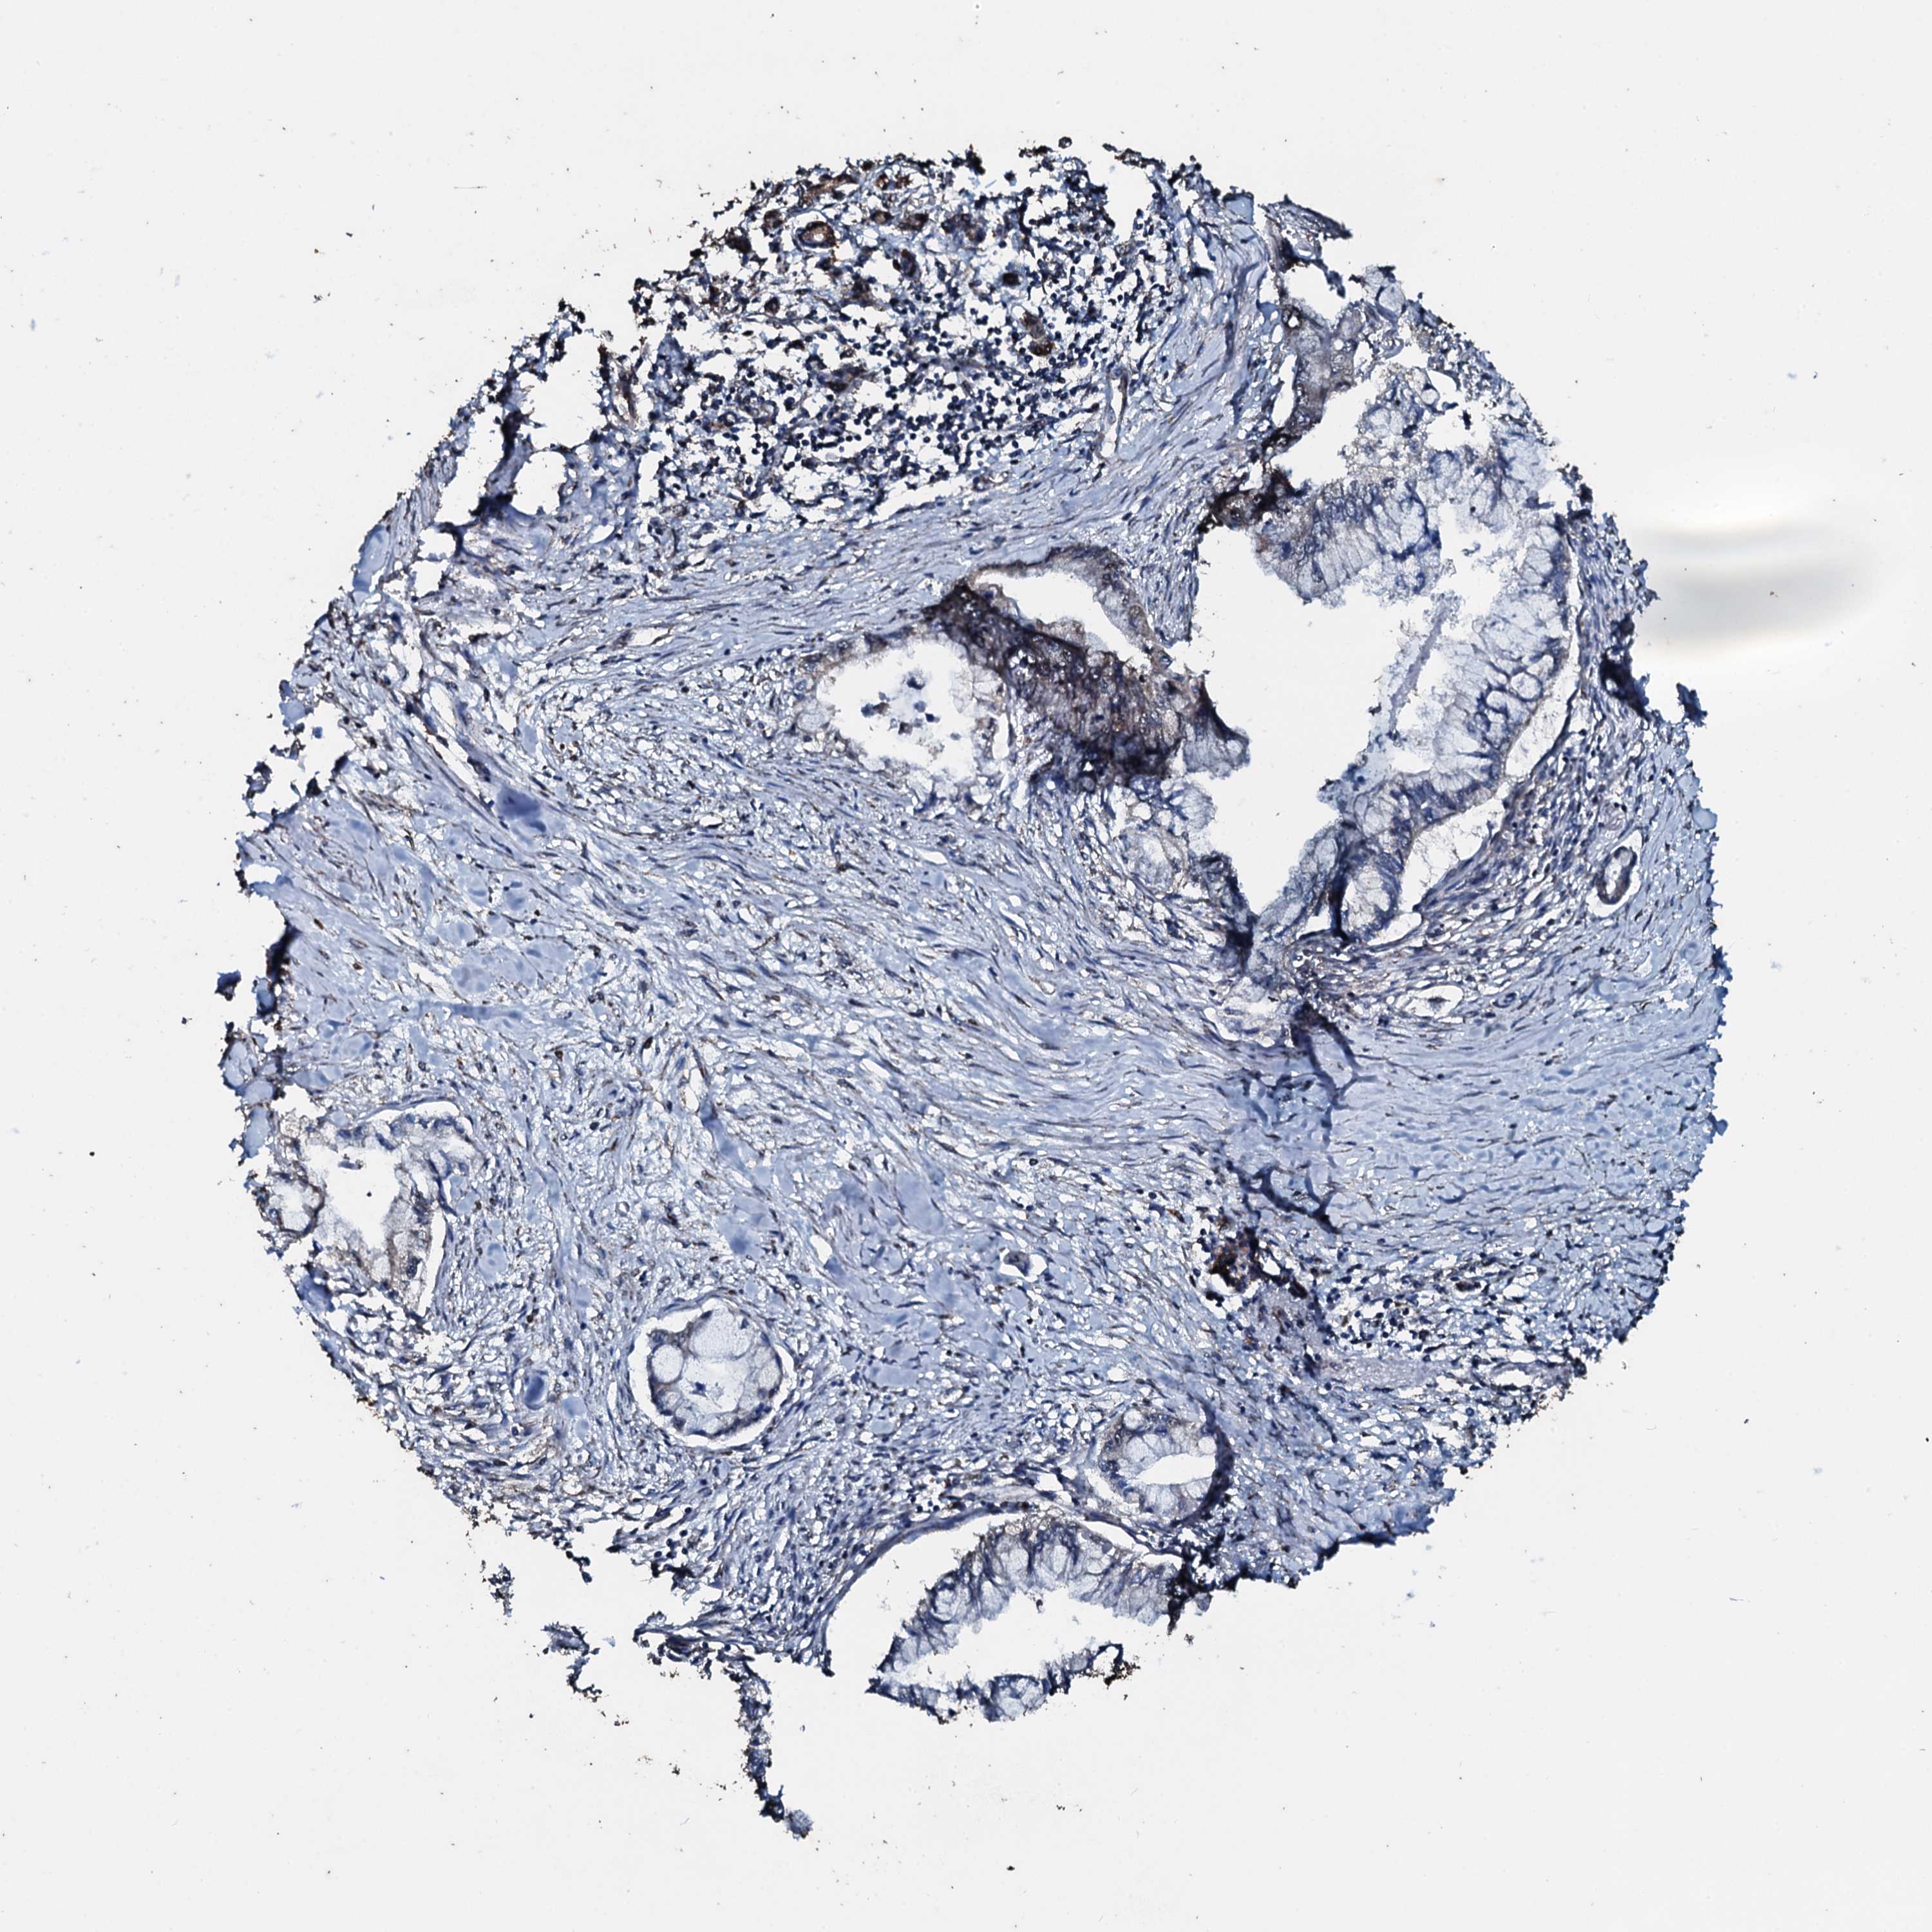

PANCREATIC CANCER - Protein expressioni

A mouse-over function shows sample information and annotation data. Click on an image to view it in a full screen mode. Samples can be filtered based on level of antibody staining by selecting one or several of the following categories: high, medium, low and not detected. The assay and annotation is described here.

Note that samples used for immunohistochemistry by the Human Protein Atlas do not correspond to samples in the TCGA dataset.

Antibody stainingi

Antibody staining in the annotated cell types in the current human tissue is reported as not detected, low, medium, or high, based on conventional immunohistochemistry profiling in selected tissues. This score is based on the combination of the staining intensity and fraction of stained cells.

Each image is clickable and will lead to virtual microscopy that enables deeper exploration of all samples and also displays staining intensity scores, fraction scores and subcellular localization as well as patient and tissue information for each sample.

Antibody HPA041168

Staining

High

Medium

Low

Not detected

Intensity

Strong

Moderate

Weak

Negative

Quantity

>75%

75%-25%

<25%

None

Location

Nuclear

Cytoplasmic/membranous

Cytoplasmic/membranous,nuclear

Adenocarcinoma, NOS